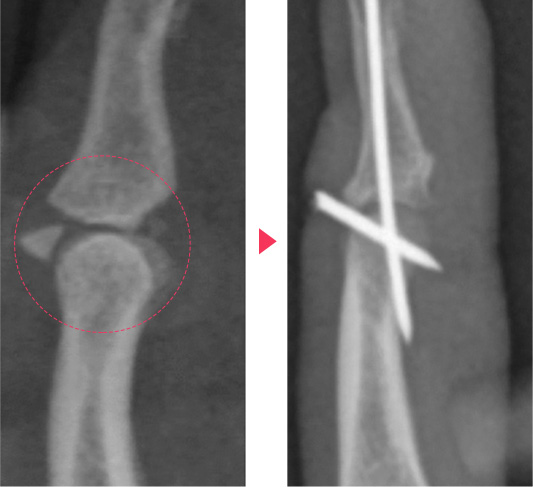

뼈가 부러져서 어긋난 경우 정밀한 조작을 통해 올바른 위치로 되돌린 후

석고부목을 사용하여 고정된 상태를 유지합니다.

그러나 이러한 치료에도 고정이 잘 이루어지지 않는다면 국소마취하에

간단한 핀고정술로 고정력을 높일 수 있습니다.